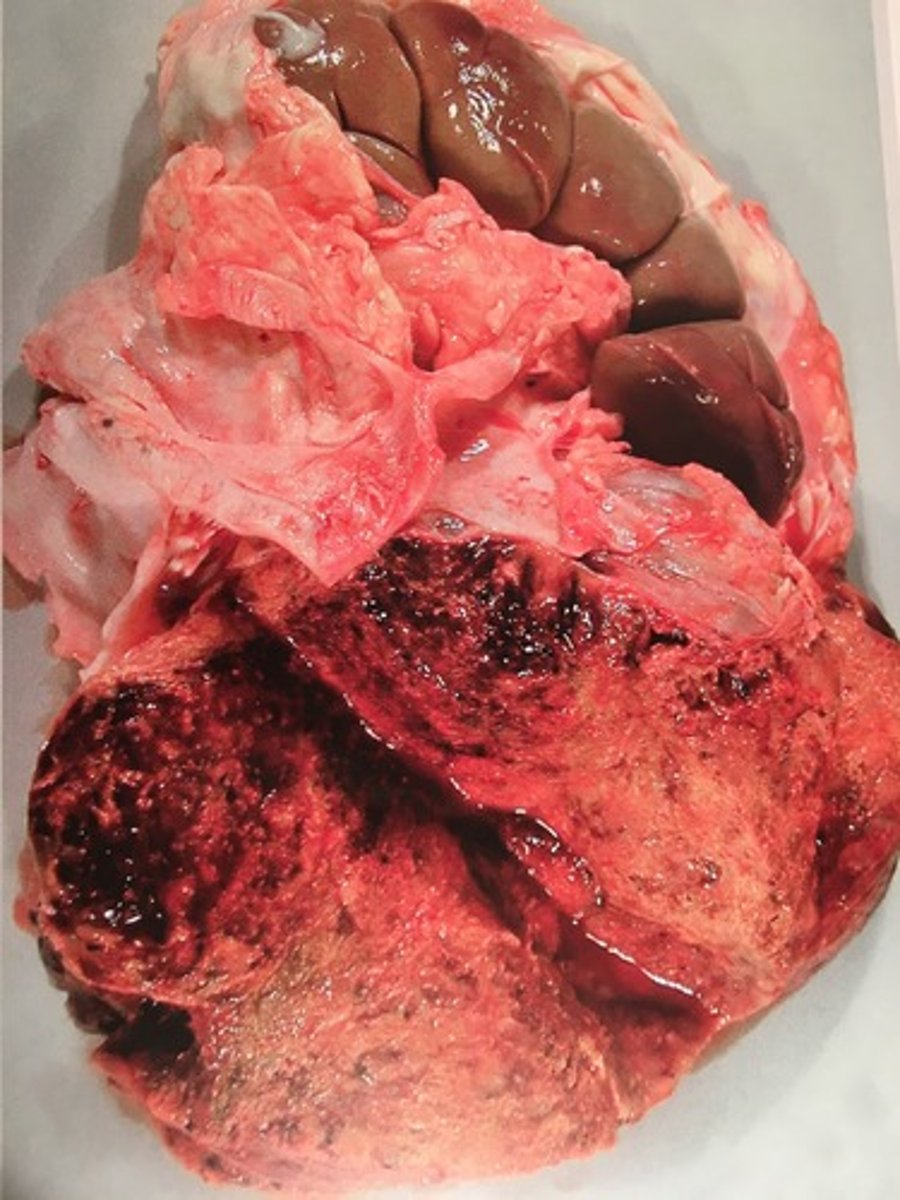

Adrenocortikal adenoma (med hemorrhagi og mineralisering)

adrenal kirtel (binyrer) og lever fra kvæg, hvad er den patoanatomiske diagnose?